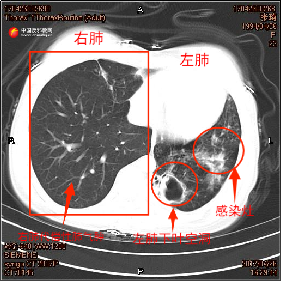

2018年4月第二次确诊肺结核时,张琦的痰培养结果证实其合并烟曲霉菌感染,时任住院医生张洋回忆起当时的治疗困境称:“张琦第二次确诊为复发性耐药肺结核,我们为她制定了针对性治疗方案,并增加了抗真菌的口服药。”治疗期间张琦多次拍摄的胸部CT片,也记录了其左肺病情恶化。张琦左肺下叶空洞逐渐变大,肺叶萎缩,感染逐渐加重。

▲左图为张琦2017年4月胸部CT,右图为张琦2018年4月胸部CT